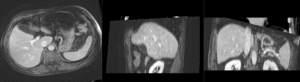

insufficient mask: nonrigid registered with liver mask only, note the misalignment in the remaining abdomen

Color overlay of registered MRI onto CT, illustrating the fusion: MRI soft tissue contrast shows substructures & vasculature invisible on the CT